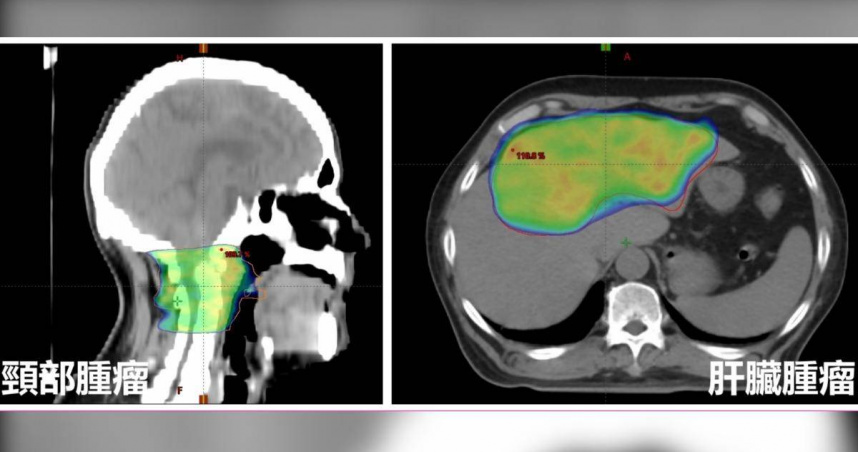

台中一名男子「麻糬伯」因癱瘓就醫,竟發現癌細胞擴散到頸椎,且肝臟內有一顆20公分的巨型腫瘤。(圖/亞大附醫提供)

王博民指出,隨後他開始處理肝癌,他發現麻糬伯的肝臟內有一顆20公分的巨型腫瘤,大小有如一顆排球,已經阻塞左肝門靜脈。所幸醫療團隊採用免疫療法、標靶藥物與放射治療三管齊下,才讓腫瘤縮小至8公分,失去活性,無須進一步手術處理或引流,麻糬伯也逐漸恢復行動力,生活回到正軌。